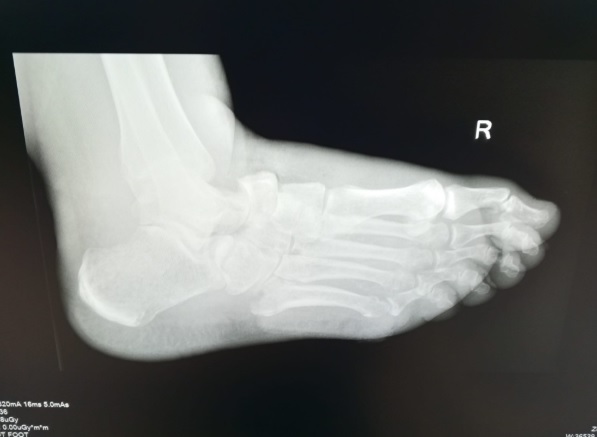

- Röntgen: Ayak ve ayak bileğinde kemik kırıkları, eklem boşluğu daralmaları ve deformiteleri gösterebilir.